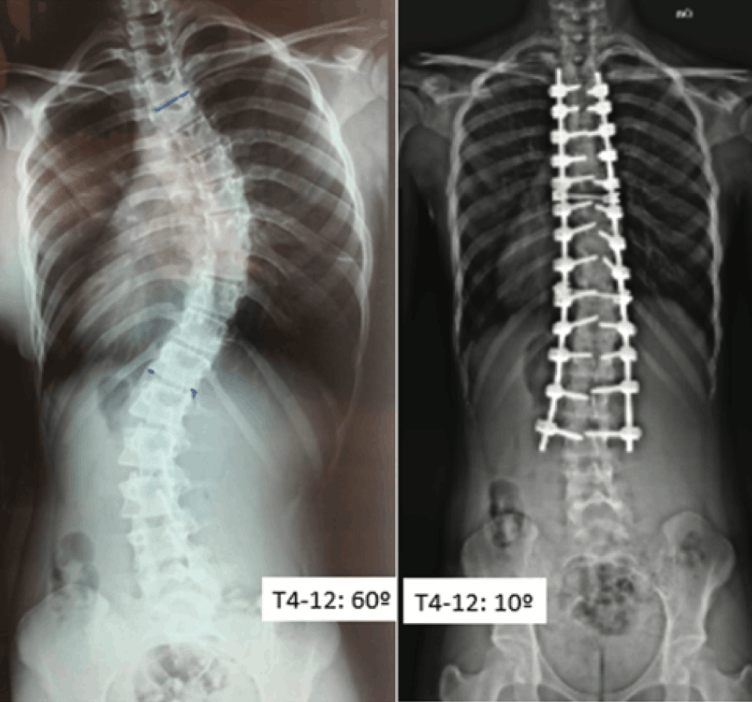

This retrospective study analyzed 52 patients who underwent scoliosis surgery between 2014 and 2023 in private hospitals in the Central-West region of Brazil. The objective was to evaluate the degree of curvature correction, using the Cobb method, and postoperative complications. The sample was predominantly female (86.6%), with a mean age of 16 years. The majority of patients (92.3%) were diagnosed with idiopathic scoliosis (IS), with 57.7% presenting thoracic curves and 34.6% presenting lumbar curves, according to the Lenke classification.

The average preoperative Cobb angle was 55°, with a postoperative average correction of 74%, reflecting the effectiveness of spinal arthrodesis techniques with pedicle screws.